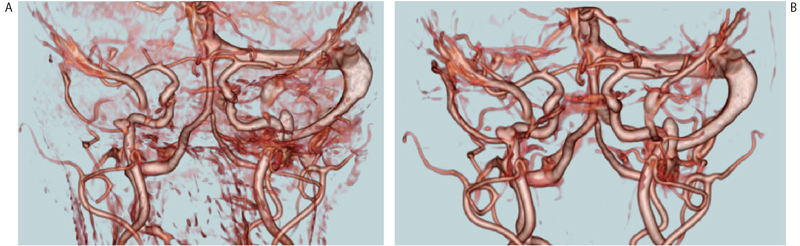

図4 変形医用画像統合によるアンギオ差分画像(AZE社,VirtualPlace) Aは改良前,Bは改良後であり,改良後はノイズが減少している。AZE社とハーバード大学の共同研究開発を3D Slicerで行った後,商用ソフトウェア「VirtualPlace」に移植された。

図4 変形医用画像統合によるアンギオ差分画像(AZE社,VirtualPlace)

Aは改良前,Bは改良後であり,改良後はノイズが減少している。AZE社とハーバード大学の共同研究開発を3D Slicerで行った後,商用ソフトウェア「VirtualPlace」に移植された。